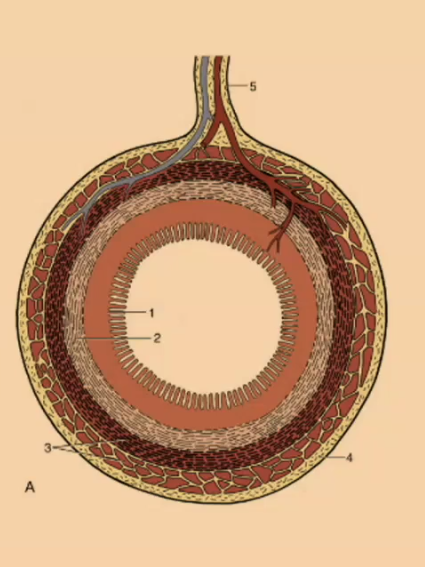

What is the outermost layer of the simple stomach?

Serosa

Serosa

What creates the mucosal folds in the simple stomach?

submucosa

What is the thinnest layer of the simple stomach wall?

Muscularis mucosa

What is the innermost layer of the simple stomach wall?

Mucosa

#1

Mucosa

#2

Submucosa

#3

Muscular (2 Layers)

#4

Serosa